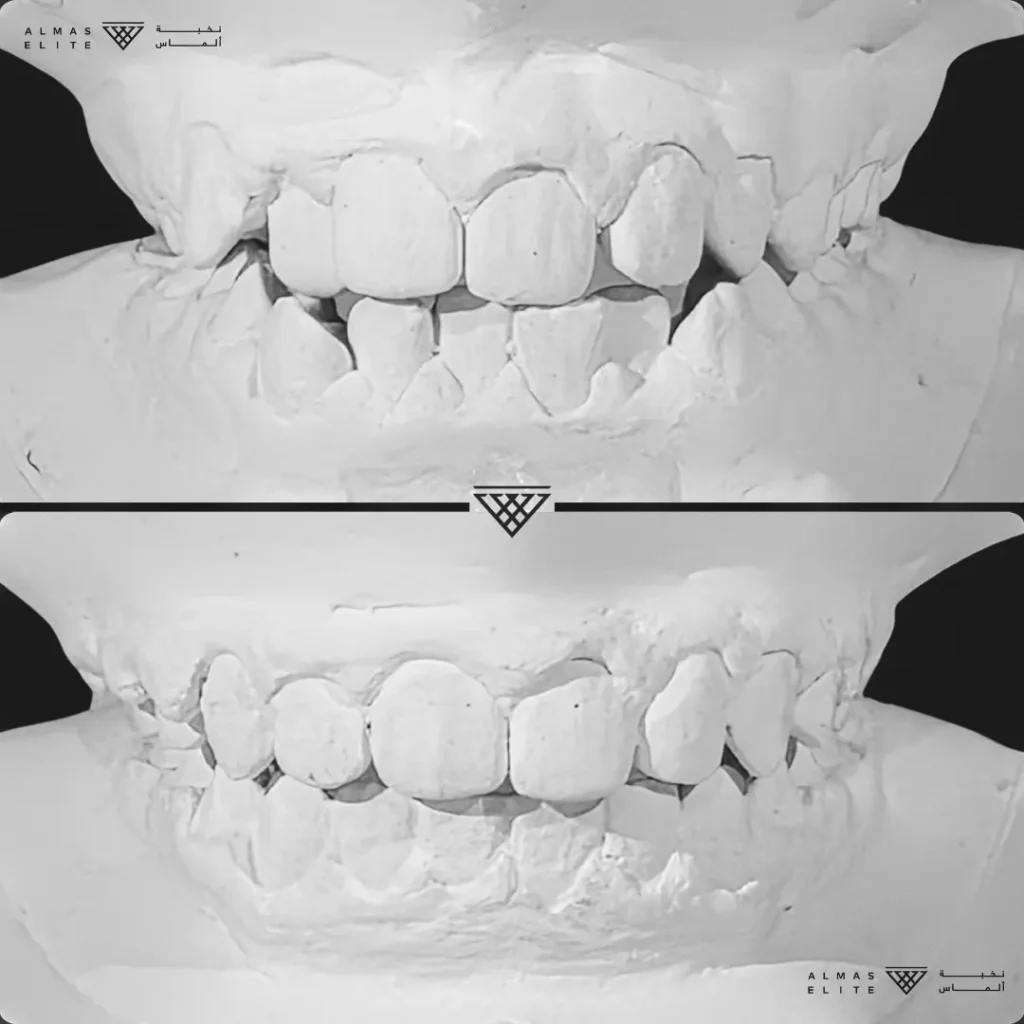

٢) التقييم والتشخيص الشامل

يشمل صور الأشعة والتحليل الرقمي للأسنان والفكين للوصول إلى تشخيص دقيق.

٣) وضع خطة علاجية مخصصة

تتضمن نوع الجهاز الأنسب، المدة المتوقعة، وتكلفة العلاج، مع شرح واضح لما يمكن توقعه أثناء رحلة التقويم.